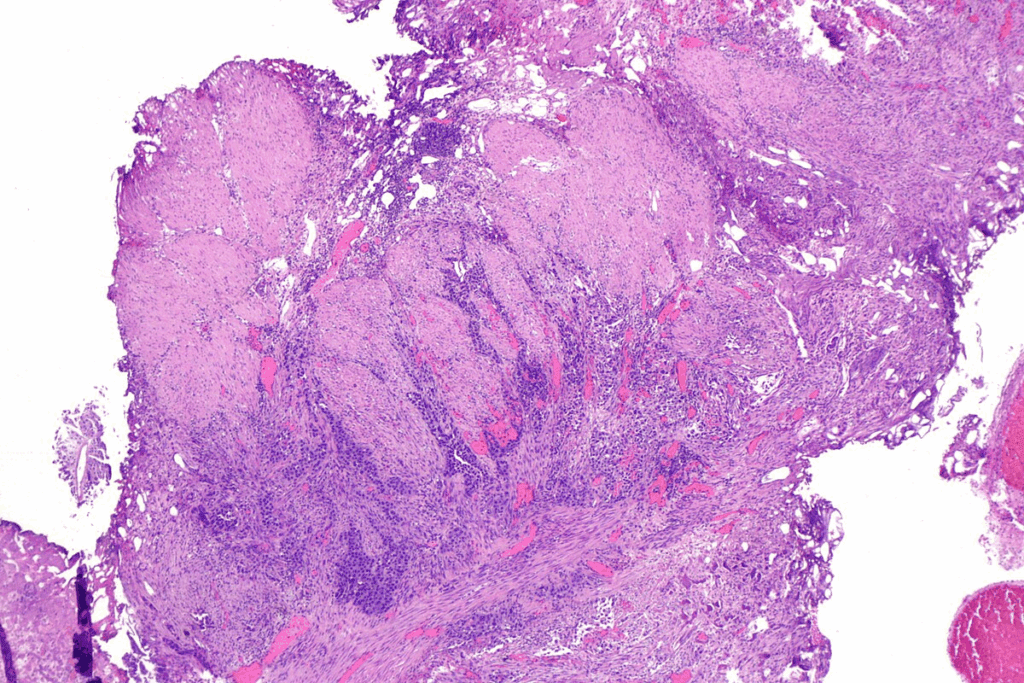

The Role of Cystoscopy in Diagnosis

Cystoscopy is a big part of the bladder polyp biopsy. It uses a thin tube with a camera to look at the bladder lining. Doctors can spot any areas that need a biopsy.

Cystoscopy Procedure: We use a cystoscope to see inside the bladder. The cystoscope has a camera that shows images on a screen. This lets us see the bladder lining clearly.

How Tissue Samples Are Collected

After finding suspicious areas, we take tissue samples. We use special tools through the cystoscope to do this.

These samples go to a lab for examination. They look at the tissue under a microscope. This checks for any abnormal cell growth or cancer.

The lab checks your biopsy sample carefully. Pathologists look at the tissue under a microscope for any odd cell growth or cancer. They stain the samples to see the cells better and compare them to normal bladder tissue.